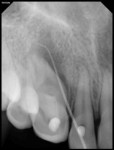

A 17-year-old healthy female was referred for the management of a persistent vestibular sinus tract in the periapical area labially in relation to the permanent maxillary right canine (tooth No. 6). The patient’s general dentist had started root-canal treatment of teeth Nos. 6 and 7 but did not complete the treatment. Tracer radiographic examination revealed the origin of the sinus tract to be in the apical end of an invagination with respect to tooth No. 6 (Figure 1 and Figure 2). This invagination extended into the root surface apically and was associated with large peri-invagination radiolucency.